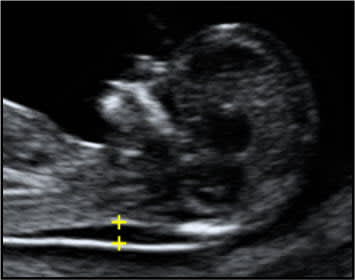

Nt エコー

先天異常部より Nt Nuchal Translucency について 医療者向け 日本産婦人科医会

Nt Nuchal Translucency ある産婦人科医のひとりごと

14 初期の超音波マーカー検査 日本産婦人科医会

02 妊娠初期 胎児の頸部浮腫 Nt 妊娠11 13週でcheck 深谷産婦人科 医学情報

胎児超音波ーマーカー検査とは ヒロクリニック

胎児の首の後ろのむくみ 浮腫 Nt とは 妊娠初期 All About

Nt Nuchal Translucency について 出生前検査 Nipt 遺伝カウンセリング 妊婦健診 エコー検査 産科 婦人科 産婦人科

胎児の首の後ろのむくみ 浮腫 Nt とは 妊娠初期 All About

胎児の首のむくみ Nt クリフム夫律子マタニティクリニック

Nt Nuchal Translucency ある産婦人科医のひとりごと